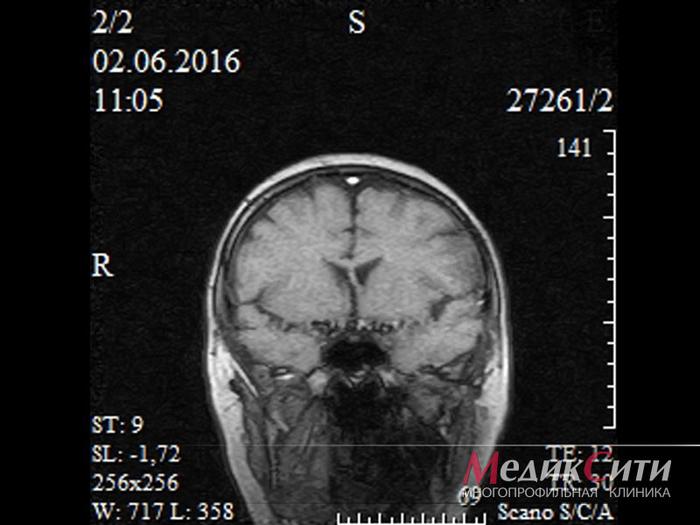

МРТ головного мозга

МРТ головного мозга

МРТ головного мозга